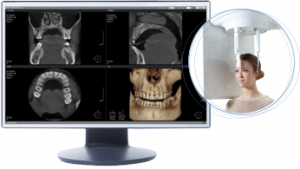

Il Tomografo Cone Beam (detto anche CBCT Tomografia Computerizzata Cone Beam) è un macchinario in grado di ottenere immagini del massiccio facciale attraverso l’emissione di una dose molto bassa di raggi X, restituendo immagini 3D di altissima qualità delle ossa mascellari e dei denti.

Il Tomografo Cone Beam (detto anche CBCT Tomografia Computerizzata Cone Beam) è un macchinario in grado di ottenere immagini del massiccio facciale attraverso l’emissione di una dose molto bassa di raggi X, restituendo immagini 3D di altissima qualità delle ossa mascellari e dei denti.

L’esame eseguito con il Tomografo Cone Beam è molto flessibile risultando dunque necessario, per differenti tipologie di impiego tra le quali:

- Pianificazione terapeutica mediante trattamenti implantari

- Programmazione di chirurgia implatare guidata

- Follow up di trattamenti implantari

- Individuazione di fistole, sinusite mascellare odontogena e processi infiammatori periradicolari

- Studio anomalie della dentizione (anomalie di posizione dei denti del giudizio o dei canini)

- Studio di aree di sclerosi e disomogeneità ossea dei mascellari

- Studio in 3D delle articolazioni temporo-mandibolari

- Studio in 3D dei seni mascellari